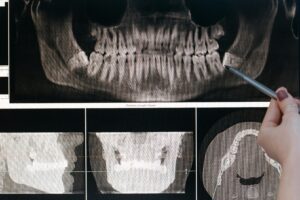

Цифровая рентгенография и КТ : обеспечивают точную визуализацию зубных дуг и челюстей для планирования протезирования.